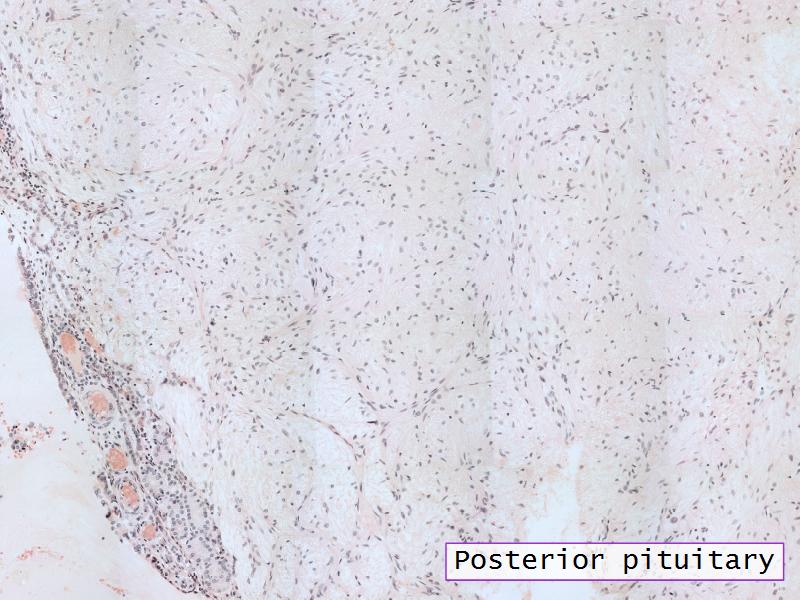

- F2: Pituicytes

- F2: Pituicytes = pars nervosa of the posterior pituitary

- Slide 52: Pituitary gland

Pituitary gland

How does the pituitary and hypothalamus communicate?2 ways